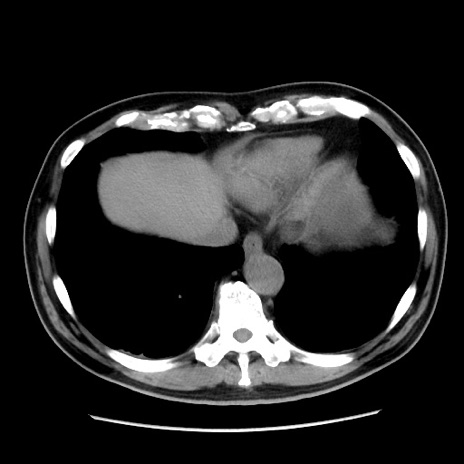

症例16(横断像)

【症例】 70歳代男性

【主訴】 腹痛、嘔吐

【現病歴】 約1ヶ月前より間欠的に腹痛と嘔吐あり、当院消化器内科を受診したところCTで多発する肝臓のLDAを指摘され、精査中であった。以降は消化器症状は安定していたが、2日前より嘔気と腹痛があり、同日より排便・排ガスが消失した。改善認めず、 本日、救急外来を受診した。

【既往歴】 大腸ポリープ切除後。

【身体所見】意識清明・会話良好、BT 36.3℃、BP 127/80mmHg、 P 80bpm、腹部:膨満あり、平坦・軟、上腹部正中および下腹部正中に圧痛あり、反跳痛なし、筋性防御なし。

【データ】WBC 7200、CRP 0.77